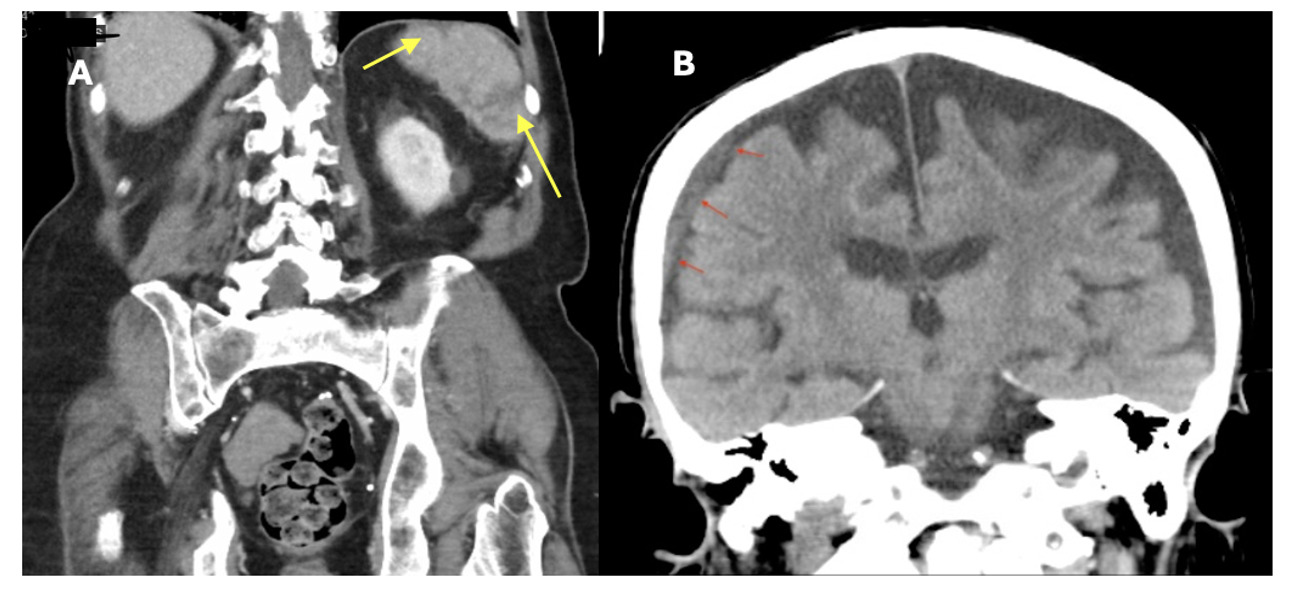

Laboratory analysis was pertinent for hemoglobin of 12.5 g/dL (normal,13.5-16.0 g/dL), platelet count of 34,000 /mm3 (normal,150-400 x109 plt/mm3), lactate dehydrogenase of 344 IU/L (normal, 100-220 IU/L), a d-dimer of 672 ng/mL (normal, 0-300 ng/ml), and haptoglobin of <8 mg/dL (normal, 40-268 mg/dL). Urinalysis was positive for 2+ blood and 2+ urobilinogen, but no casts. Blood parasite smear was positive for intraerythrocytic ring form parasites consistent with Babesia microti (Figure 1) and he was started on azithromycin and atovaquone for ten days. Doxycycline was also administered for empiric coverage of Lyme disease and anaplasmosis, which was discontinued once these serologies were confirmed to be negative. Initial parasitemia level was 1.06%. Computed tomography of the abdomen and pelvis without contrast revealed a small wedge-shaped area within the spleen, consistent with a splenic infarct (Figure 2). Though no echocardiogram was performed to formally confirm the absence of infective endocarditis or cardiac emboli, there was high clinical suspicion that this infarct was caused by Babesia microti infection. It is important to note that this patient developed a splenic infarct while taking apixaban. Although novel oral anticoagulants are effective at decreasing the risk of recurrence of venous thromboembolism, they do not completely eliminate the risk. In the presence of a transient risk factor, such as an increased inflammatory state associated with infection, patients may develop “breakthrough” thrombosis, as the temporary hypercoagulable state outweighs the protective effects of anticoagulation therapy.1 His clinical status improved following treatment with azithromycin, atovaquone, and doxycycline. Anticoagulation with apixaban was continued throughout the hospitalization. A repeat blood smear two weeks after discharge showed an undetectable parasitemia level.

A 75-year-old man with chronic obstructive pulmonary disease (COPD), hypertension, hyperlipidemia, and trigeminal neuralgia presented to urgent care with generalized fatigue, myalgias, subjective fevers, and worsening neuralgia for one week following a golf outing. Peripheral smear revealed a parasitemia level of 8% with a subset of altered, mature red blood cells infected by 1-4 (“tetrad”) small ring parasites consistent with Babesia microti infection. He was started on atovaquone, azithromycin, and empiric doxycycline coverage. His parasitemia level trended from 8% to 16.85% despite receiving this regimen for three days, thus he was switched to quinine and clindamycin and was transferred to a tertiary care hospital for possible exchange transfusion. His platelets continued to fall to 20,000/mm3 and his hemoglobin declined to 10.5 g/dL. A CT of the chest, abdomen, and pelvis with IV contrast revealed a wedge-shaped splenic hypodensity consistent with infarct (Figure 3). Echocardiogram was not suggestive of infective endocarditis or cardiac emboli as the source of infarction. Exchange transfusion was deferred in favor of transitioning his therapy from quinine and clindamycin to atovaquone and azithromycin. He was also treated with doxycycline for presumed anaplasmosis during this time.

Laboratory analysis was notable for an AST of 95 IU/L and ALT of 74 IU/L, a white blood cell count of 2.5x 109/L (normal, 4.2-10.0 x 109), hemoglobin of 10.3 g/dL, and a platelet count of 23,000 plt/mm3. His respiratory pathogen panel and urine legionella were negative. Peripheral blood smear was positive for intraerythrocytic ring form parasites, with an initial parasitemia level of 0.81%. CT abdomen pelvis with IV contrast demonstrated multiple splenic infarcts and trace perisplenic fluid (Figure 4). These infarcts were attributed to babesiosis infection, though no echocardiogram was performed to formally confirm absence of infectious endocarditis or cardiac emboli. He was started on atovaquone and azithromycin to treat Babesia microti and was empirically treated with doxycycline for other tick-borne diseases including anaplasmosis, ehrlichiosis, and Lyme Disease. He was also started on piperacillin-tazobactam to cover for other occult infection sources in the setting of severe sepsis. Anticoagulation was not recommended for his multiple splenic infarcts due to thrombocytopenia. Due to an abrupt change in mental status, a CT brain without IV contrast was performed and revealed a 6 mm right-sided subdural hematoma. A repeat CT brain without IV contrast 6 hours later confirmed the stability of this hematoma, and he was transfused one dose of platelets in the setting of an intracranial hemorrhage.